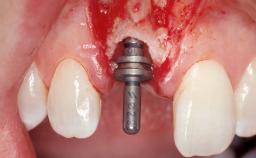

Late Placement of an Implant in a Maxillary Left Central Incisor Site

A 36-year-old female patient was referred for the replacement of the upper left central incisor (tooth 21), which had fractured. Although the tooth had been asymptomatic for many years, the crown began to loosen, at which time she presented to her dentist for an assessment. Teeth 21 and 22 had both been endodontically treated many years previously. She was a healthy individual and a non-smoker.

Bone Augmentation Horizontal|Staged

Augmentation Materials Xenogenous|Membrane

Bone Volume Deficient horizontally, requiring prior grafting